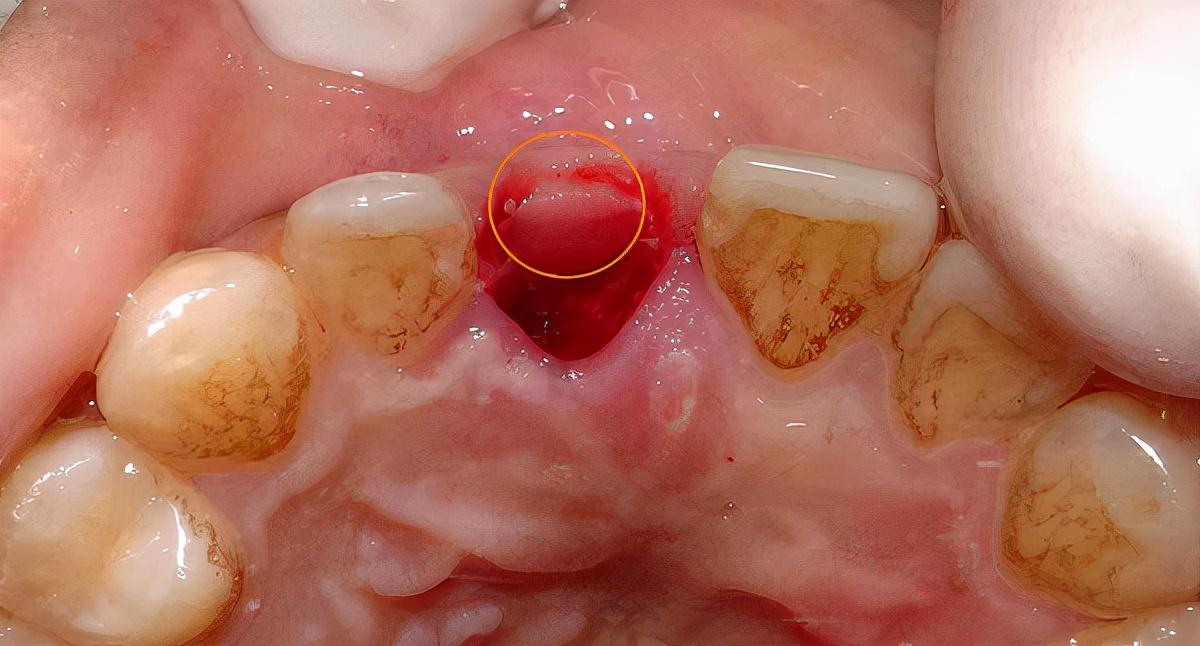

口內(nèi)照:

備洞,準備植入種植體